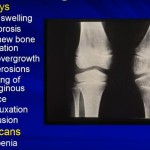

Juvenile Rheumatoid Arthritis: Pitfalls in diagnosis & Management

By Dr. R Khubchandani

Courtesy: Taral Nagda, Sandeep Patwardhan, Ashok Shyam, POSICON 2012